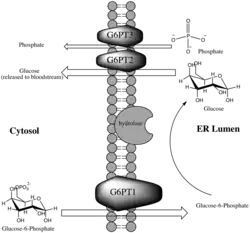

It consists of three subunits, each of which are vital components of the multi-enzyme Glucose-6-Phosphatase Complex (G6Pase). This important enzyme complex is located within the membrane of the endoplasmic reticulum, and catalyzes the terminal reactions in both glycogenolysis and gluconeogenesis.[8] The G6Pase complex is most abundant in liver tissue, but also present in kidney cells, small intestine, pancreatic islets and at a lower concentration in the gallbladder.[9][10] The G6Pase complex is highly involved in the regulation of homeostasis and blood glucose levels. Within this framework of glucose regulation, the translocase components are responsible for transporting the substrates and products across the endoplasmic reticulum membrane, resulting in the release of free glucose into the bloodstream.[8]

Glucose-6-phosphate translocase is a transmembrane protein providing a selective channel between the endoplasmic reticulum lumen and the cytosol. The enzyme is made up of three separate transporting subunits referred to as G6PT1 (subunit 1), G6PT2 (subunit 2) and G6PT3 (subunit 3). While the hydrolyzing component of the G6Pase complex is located on the side of the membrane on which it acts, namely facing the lumen, the translocases are all integral membrane proteins in order to perform their function as cross-membrane transporters. The translocases are spatially located on either side of the active site of the hydrolyzing component within the membrane, which allows the greatest speed and facility of the reaction.[11]

Each of the translocase subunits performs a specific function in the transport of substrates and products, and finally release of glucose (which will eventually reach the bloodstream), as a step in glycogenolysis or gluconeogenesis. G6PT1 transports Glucose-6-Phosphate from the cytosol into the lumen of the endoplasmic reticulum, where it is hydrolyzed by the catalytic subunit of G6Pase. After hydrolysis, glucose and inorganic phosphate are transported back into the cytosol by G6PT2 and G6PT3, respectively.[12] While the exact chemistry of the enzyme remains unknown, studies have shown that the mechanism of the enzyme complex is highly dependent upon the membrane structure. For instance, the Michaelis Constant of the enzyme for glucose-6-phosphate decreases significantly upon membrane disruption.[13] The originally proposed mechanism of the G6Pase system involved a relatively unspecific hydrolase, suggesting that G6PT1 alone provides the high specificity for the overall reaction by selective transport into the lumen, where hydrolysis occurs. Supporting evidence for this proposed reaction includes the marked decrease in substrate specificity of hydrolysis upon membrane degradation.[13]

Figure 1 illustrates the role of G6P-Translocase within the G6Pase complex.